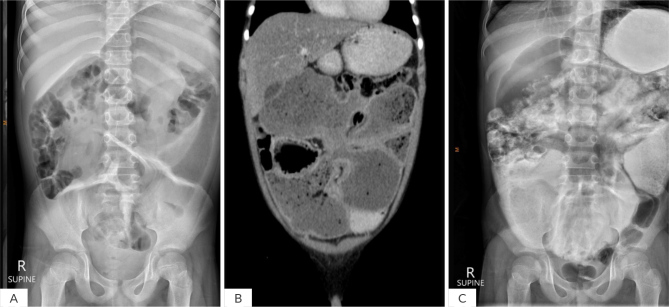

Case presentation: A 10-year-old Thai boy with haemoglobin (Hb) E trait and iron deficiency anaemia presented with significant oedema and abdominal distention. Laboratory investigations revealed isolated hypoalbuminemia. Imaging studies, including computed tomography (CT) scan, demonstrated a large, loculated, rim-enhancing air-fluid collection adjacent to the jejunum, along with mild dilatation and wall thickening of the affected jejunal loop. The patient underwent exploratory laparotomy, which included jejunal resection and jejunojejunal end-to-end anastomosis.

Learning points: Jejunal duplications are rare congenital malformations, which can cause a range of symptoms, including bilious vomiting, abdominal pain, and obstruction.Our patient presented with iron deficiency anaemia, generalized oedema, including swelling of both legs, scrotum, and abdominal distension.The diagnosis was made by computed tomography scan.